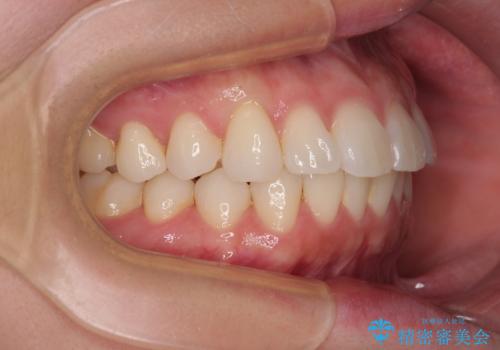

- 上下前歯の叢生を気にして来院された患者様です。

軽度な叢生であり、安価で短期間の治療を規模されていたため、インビザライン・モデレートを用いて矯正治療を行うこととしました。

インビザライン・モデレートは、製作できるアライナーの枚数に制限があるため、移動可能な量に限りがあるものの、インビザライン・ライトよりも枚数が多いため、幅広い症例に対応可能です。